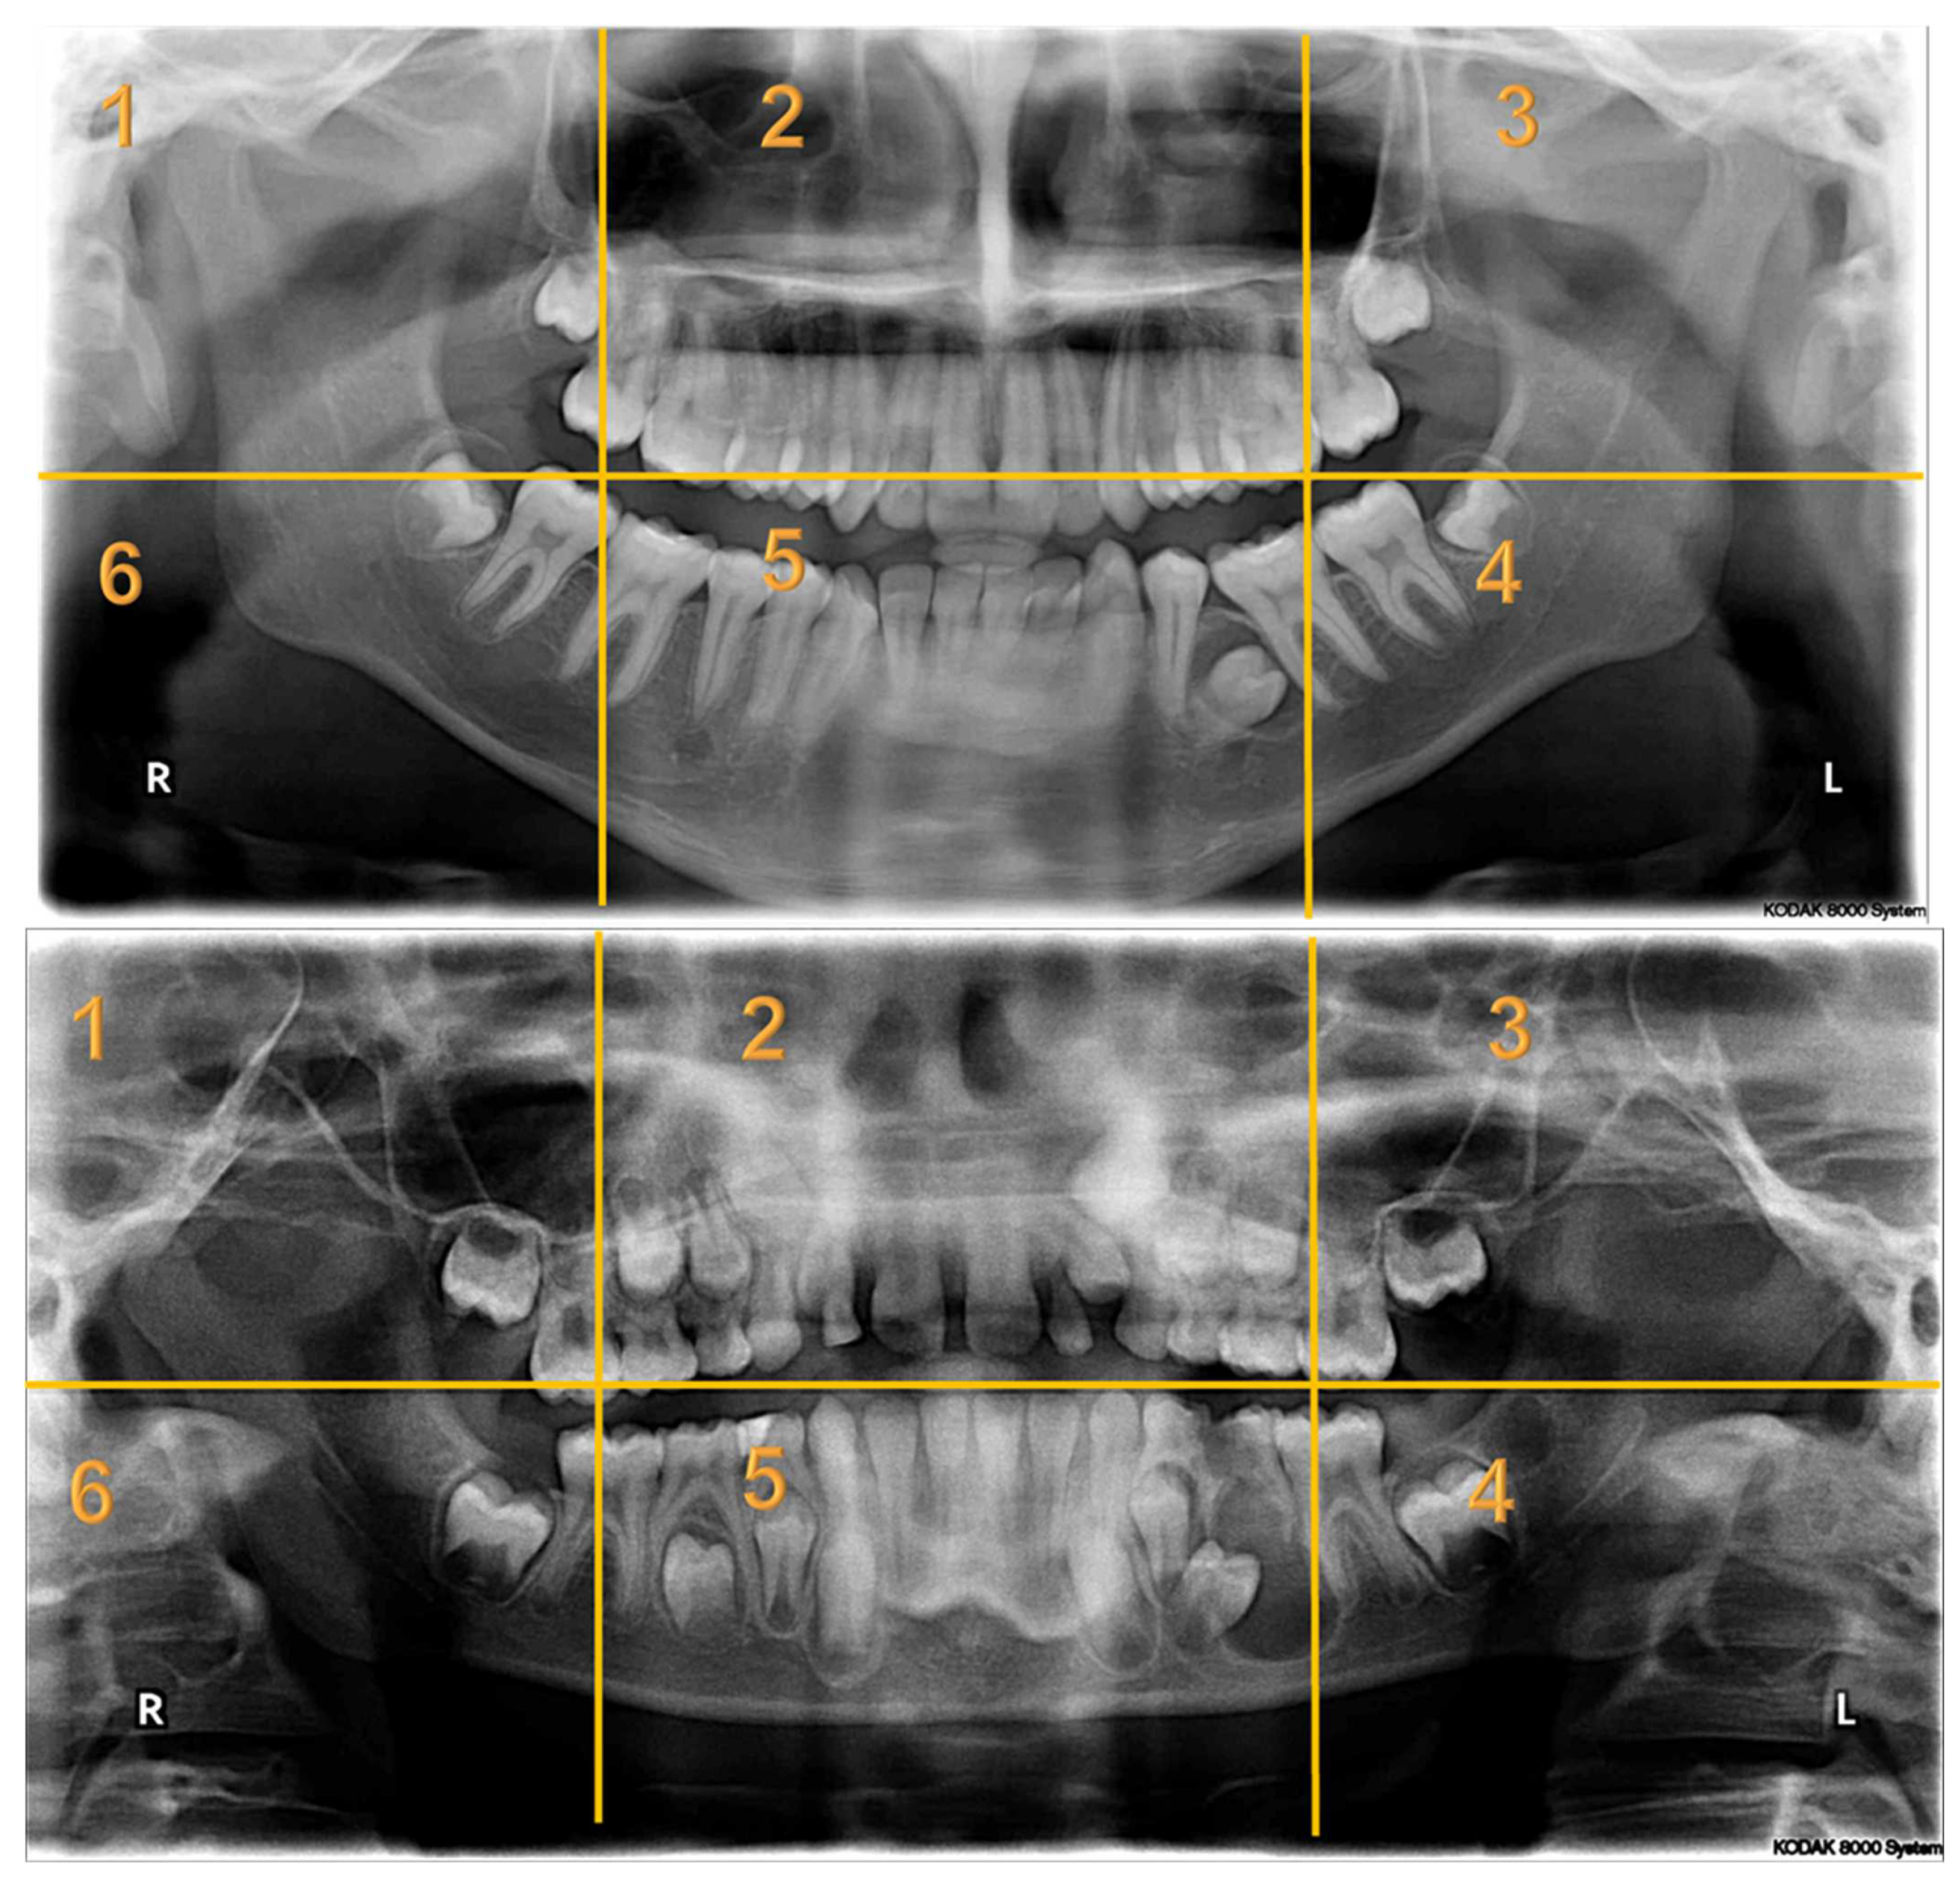

Appendix A. Radiographs Included in the Study

| Radiographs with Abnormalities | Number of Sextants Involved | Number of AOI a | Number of Participants | Total Recorded Observation b |

|---|---|---|---|---|

| Radiograph 1 | Multiple | 3 | 30 | 90 |

| Radiograph 2 | Multiple | 8 | 30 | 240 |

| Radiograph 3 | Single | 2 | 30 | 60 |

| Radiograph 4 | Single | 2 | 30 | 60 |

| Radiograph 5 | Single | 1 | 30 | 30 |

| Radiograph 6 | Single | 1 | 30 | 30 |

| Radiograph 7 | Single | 1 | 30 | 30 |

| Overall Observations | 540 |